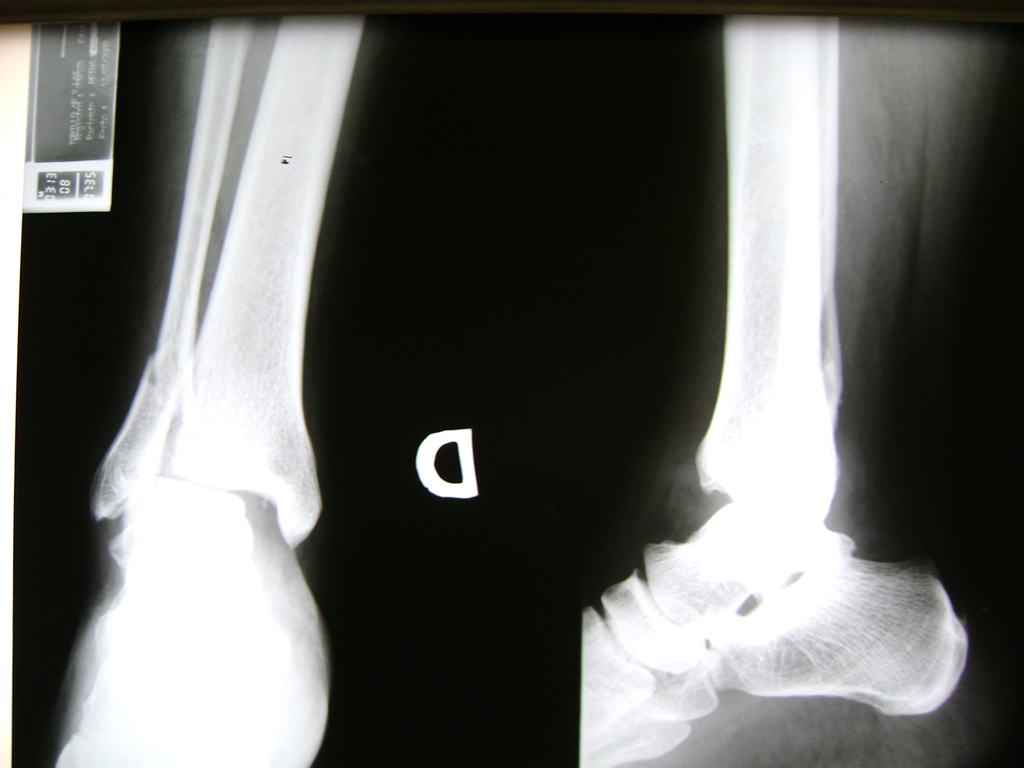

Tobillo

Detail Download